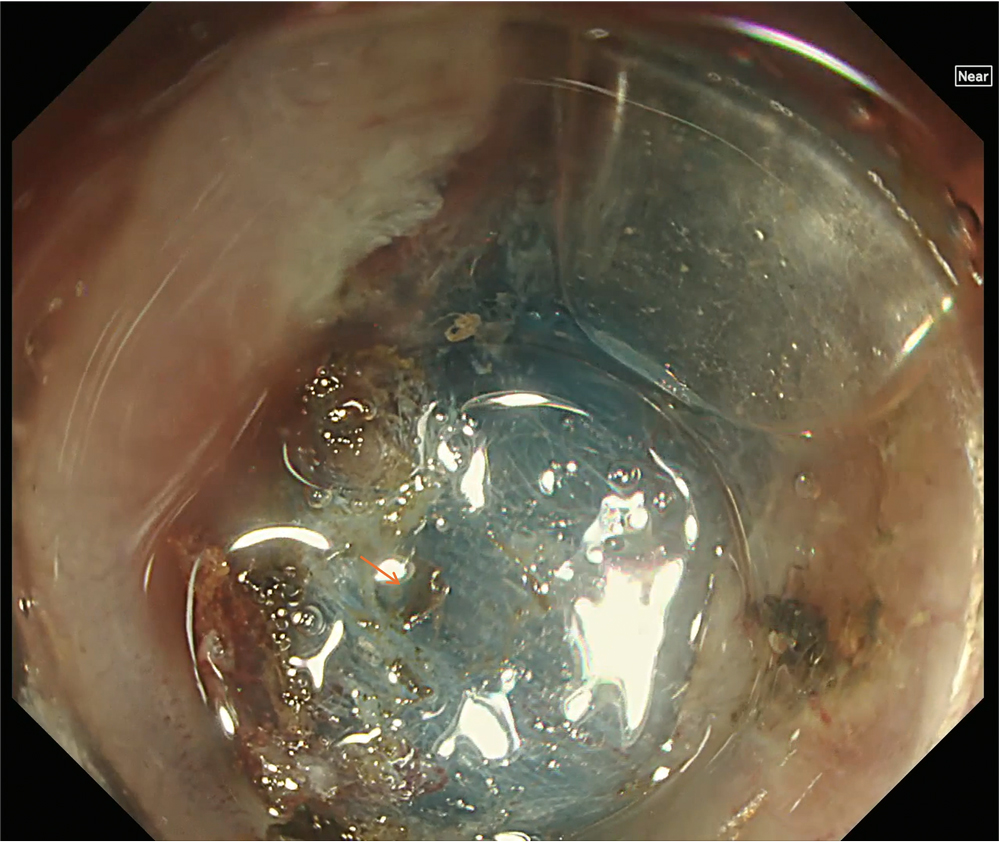

12. Hemostasis confirmed in WLI

White light imaging confirms successful hemostasis. The orange arrow indicates a coagulated clot formed after contact coagulation.